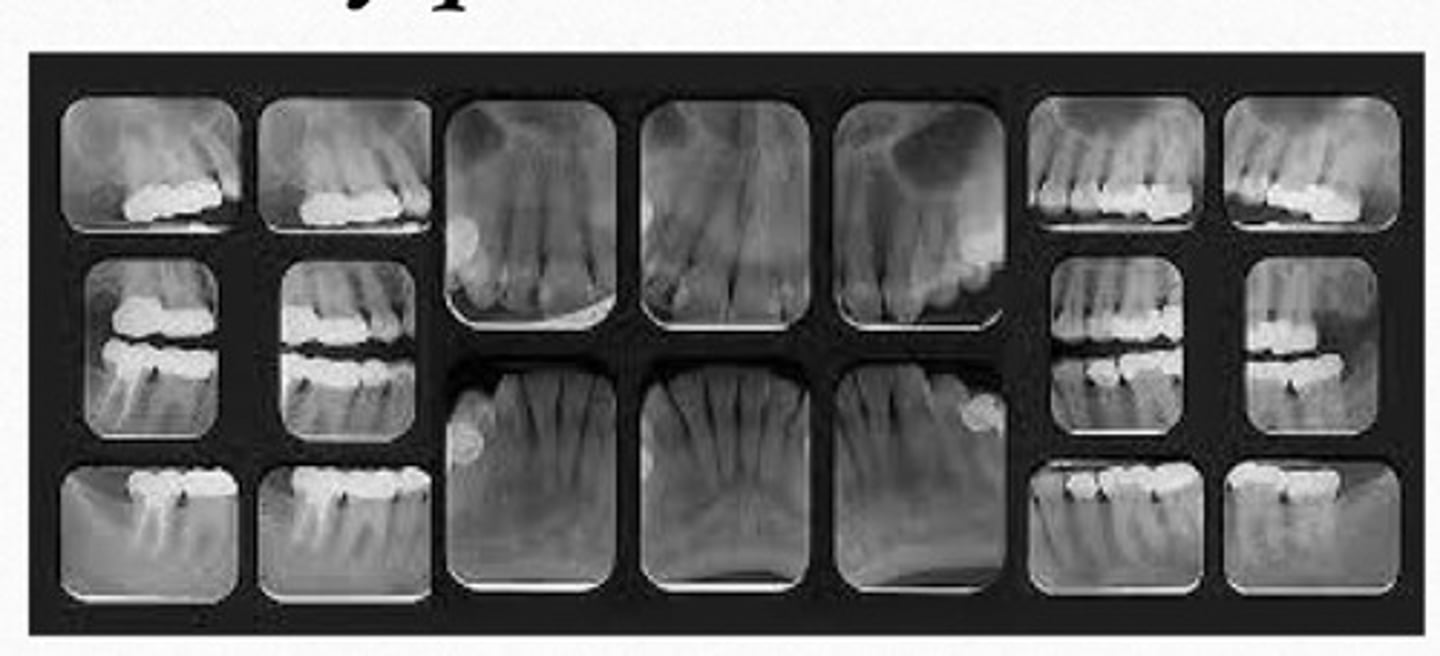

full mouth series radiograph

is composed of a series of individual images, including a combination of bitewing & periapical

purpose of full mouth series:

as a baseline on the health of your mouth